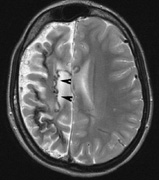

4. Cognitive impairment. Thirty percent to 60% of children with NF1 have learning difficulties, which are typically mild and nonprogressive. These include visual-spatial problem-solving difficulty, language disorders, and attention deficit disorder. The reason for this is not clear but may be related to unidentified bright objects (UBOs) seen on T2-weighted brain magnetic resonance imaging (MRI) scans. These hyperintensities are common in young patients with NF1 but decrease with advancing age. The histopathologic correlate of UBOs is unclear. It has been postulated that the prevalence of learning difficulties in children with NF1 may be related to heterozygosity of the NF1 gene (i.e., the gene may have additional functions that affect cognition when the full complement of its gene product is not expressed in the central nervous system).25,32–34

2. Subependymal nodules (SEN) are typically found along the lateral borders of the ventricles and parehncymal brain lesion (“cortical tubers”) (Figs. 14 and 15). Calcification in the first year of life is rare.132

On MRI imaging, the subependymal nodules and parenchymal brain lesions of infants (age ≤3 months) and adults show different signal characteristics. Infant CNS tubers are hyperintense on T1-weighted images and hypointense on T2-weighted images, which is the opposite of the pattern seen in adults.134 Malignant transformation of SEN occurs in about 10% to 15% of patients and the resultant subependymal giant cell astrocytoma accounts for 25% of premature deaths in TSC.135,136

Fig. 14. Tuberous Sclerosis Complex: Sub-Ependymal nodules. These are typically found along the lateral borders of the ventricles.132